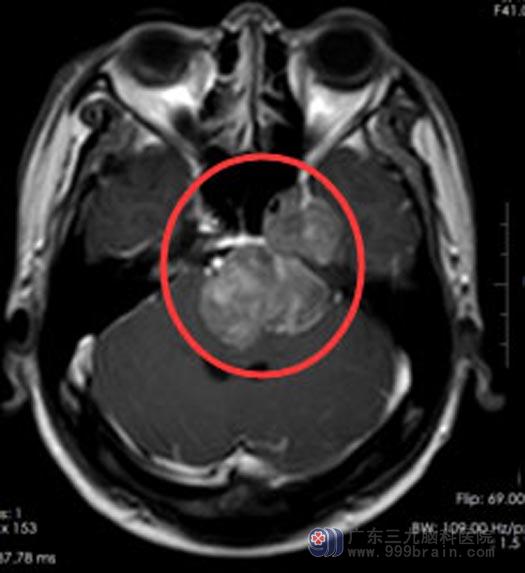

马先生三个月前出现阵发性头痛且伴有右上肢的肢体麻木感,近来总是反复地出现饮水呛咳,不能直线行走;当地医院头颅MRI检查提示:左侧桥小脑角占位性病变。

结合马先生的临床症状、体征、头颅MR检查等,综合神经外科鲁明副院长考虑他是“左侧跨中后颅窝占位,三叉神经鞘瘤可能”。由于肿瘤体积较大,周围脑组织水肿明显,有手术指征,建议行手术切除。